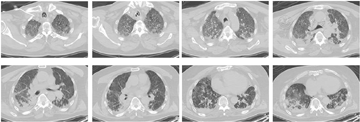

化验结果:动脉血pH 7.331,二氧化碳分压(partial pressure of carbon dioxide,PCO2) 88.5mmHg,氧分压(partial pressure of oxygen,PO2) 66.0mmHg,乳酸0.7mmol/L,血常规白细胞11.37×109/L,高敏C反应蛋白28.2mg/L;降钙素原0.59ng/ml;肝肾功、心脏生化及凝血结果基本正常。胸部CT提示:双肺斑片状及弥漫性毛玻璃样渗出,可见纤维条索样增生及肺大泡(图1)。